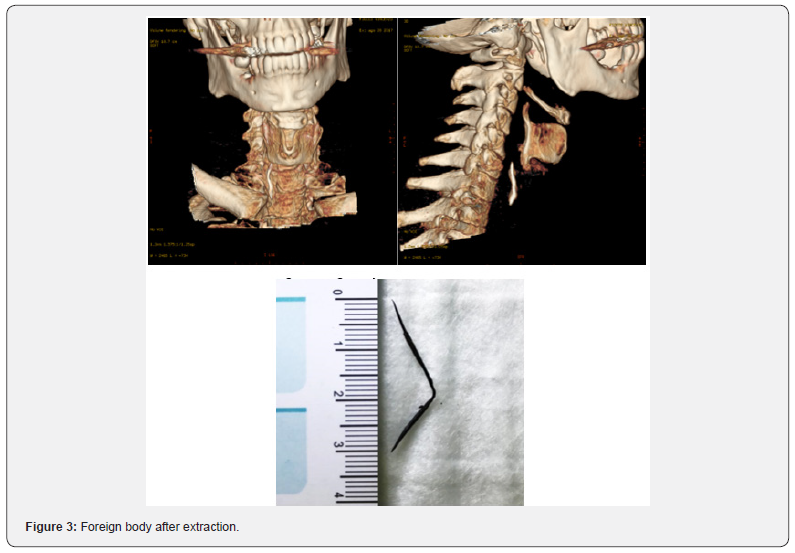

50-year-old men, V.F., presented to our ENT department due to a severe dysphagia that appeared about 5 days earlier after a fish-based lunch. The patient was convinced he had ingested a fish hook. The endoscopic evaluation of the high airways showed an important edema of the right arytenoid; the vocal cords were normal in form and motility, and no foreign body was visible. However, the X-ray of the esophageal-pharyngeal tract Figure 1 showed a suspected extraneous oesophageal body by ingestion of food and signaled, at C5-C6 level on right side of parapharyngeal wall, a 45 mm linear radiopac image. An integration with endoscopic examination was required. However, esophagogastroduodenoscopy was negative for the presence of foreign bodies,but it showed the presence of an extraneous granuloma at the level of the right arytenoid.In the same day, in general anesthesia, apanendoscopy of the superior aero-digestive tract was performed, which does not show any extraneous body at this level, except an important congestion of the right piriform sinus. At the end of the procedure, a nasal-gastric tube was due to a suspected perforation of the esophagus. At this point, the hypothesis that the right piriform sinus was been the point of entry of the foreign body became more and more concrete.A TC scan of the neck (Figure 2) was performed and it highlighted the foreign body at the right side of parapharyngeal wall, at the height of the homolateralarytenoid. Therefore, we decided to undergo a cervicotomicsurgery. In general anesthesia, cutaneous incision was performed along the margin of the sternocleidomastoid muscle, about 10 cm. The right thyroid lobe was found and lowered from the lateral wall of the trachea to the side wall of the esophagus, which had a millimetric puncture (foreign body output point). In the tracheo-esophageal sulcus, near the right recurrent nerve, the foreign body (metal wire about 5 cm in length) Figure 3 was found and removed.

a) Extraneous body (metal film) contained in the right tracheoesophageal sulcus;

b) Millimetric perforation of the side wall of the esophagus (input point of the foreign body)

c) Paresis of the right vocal cord.